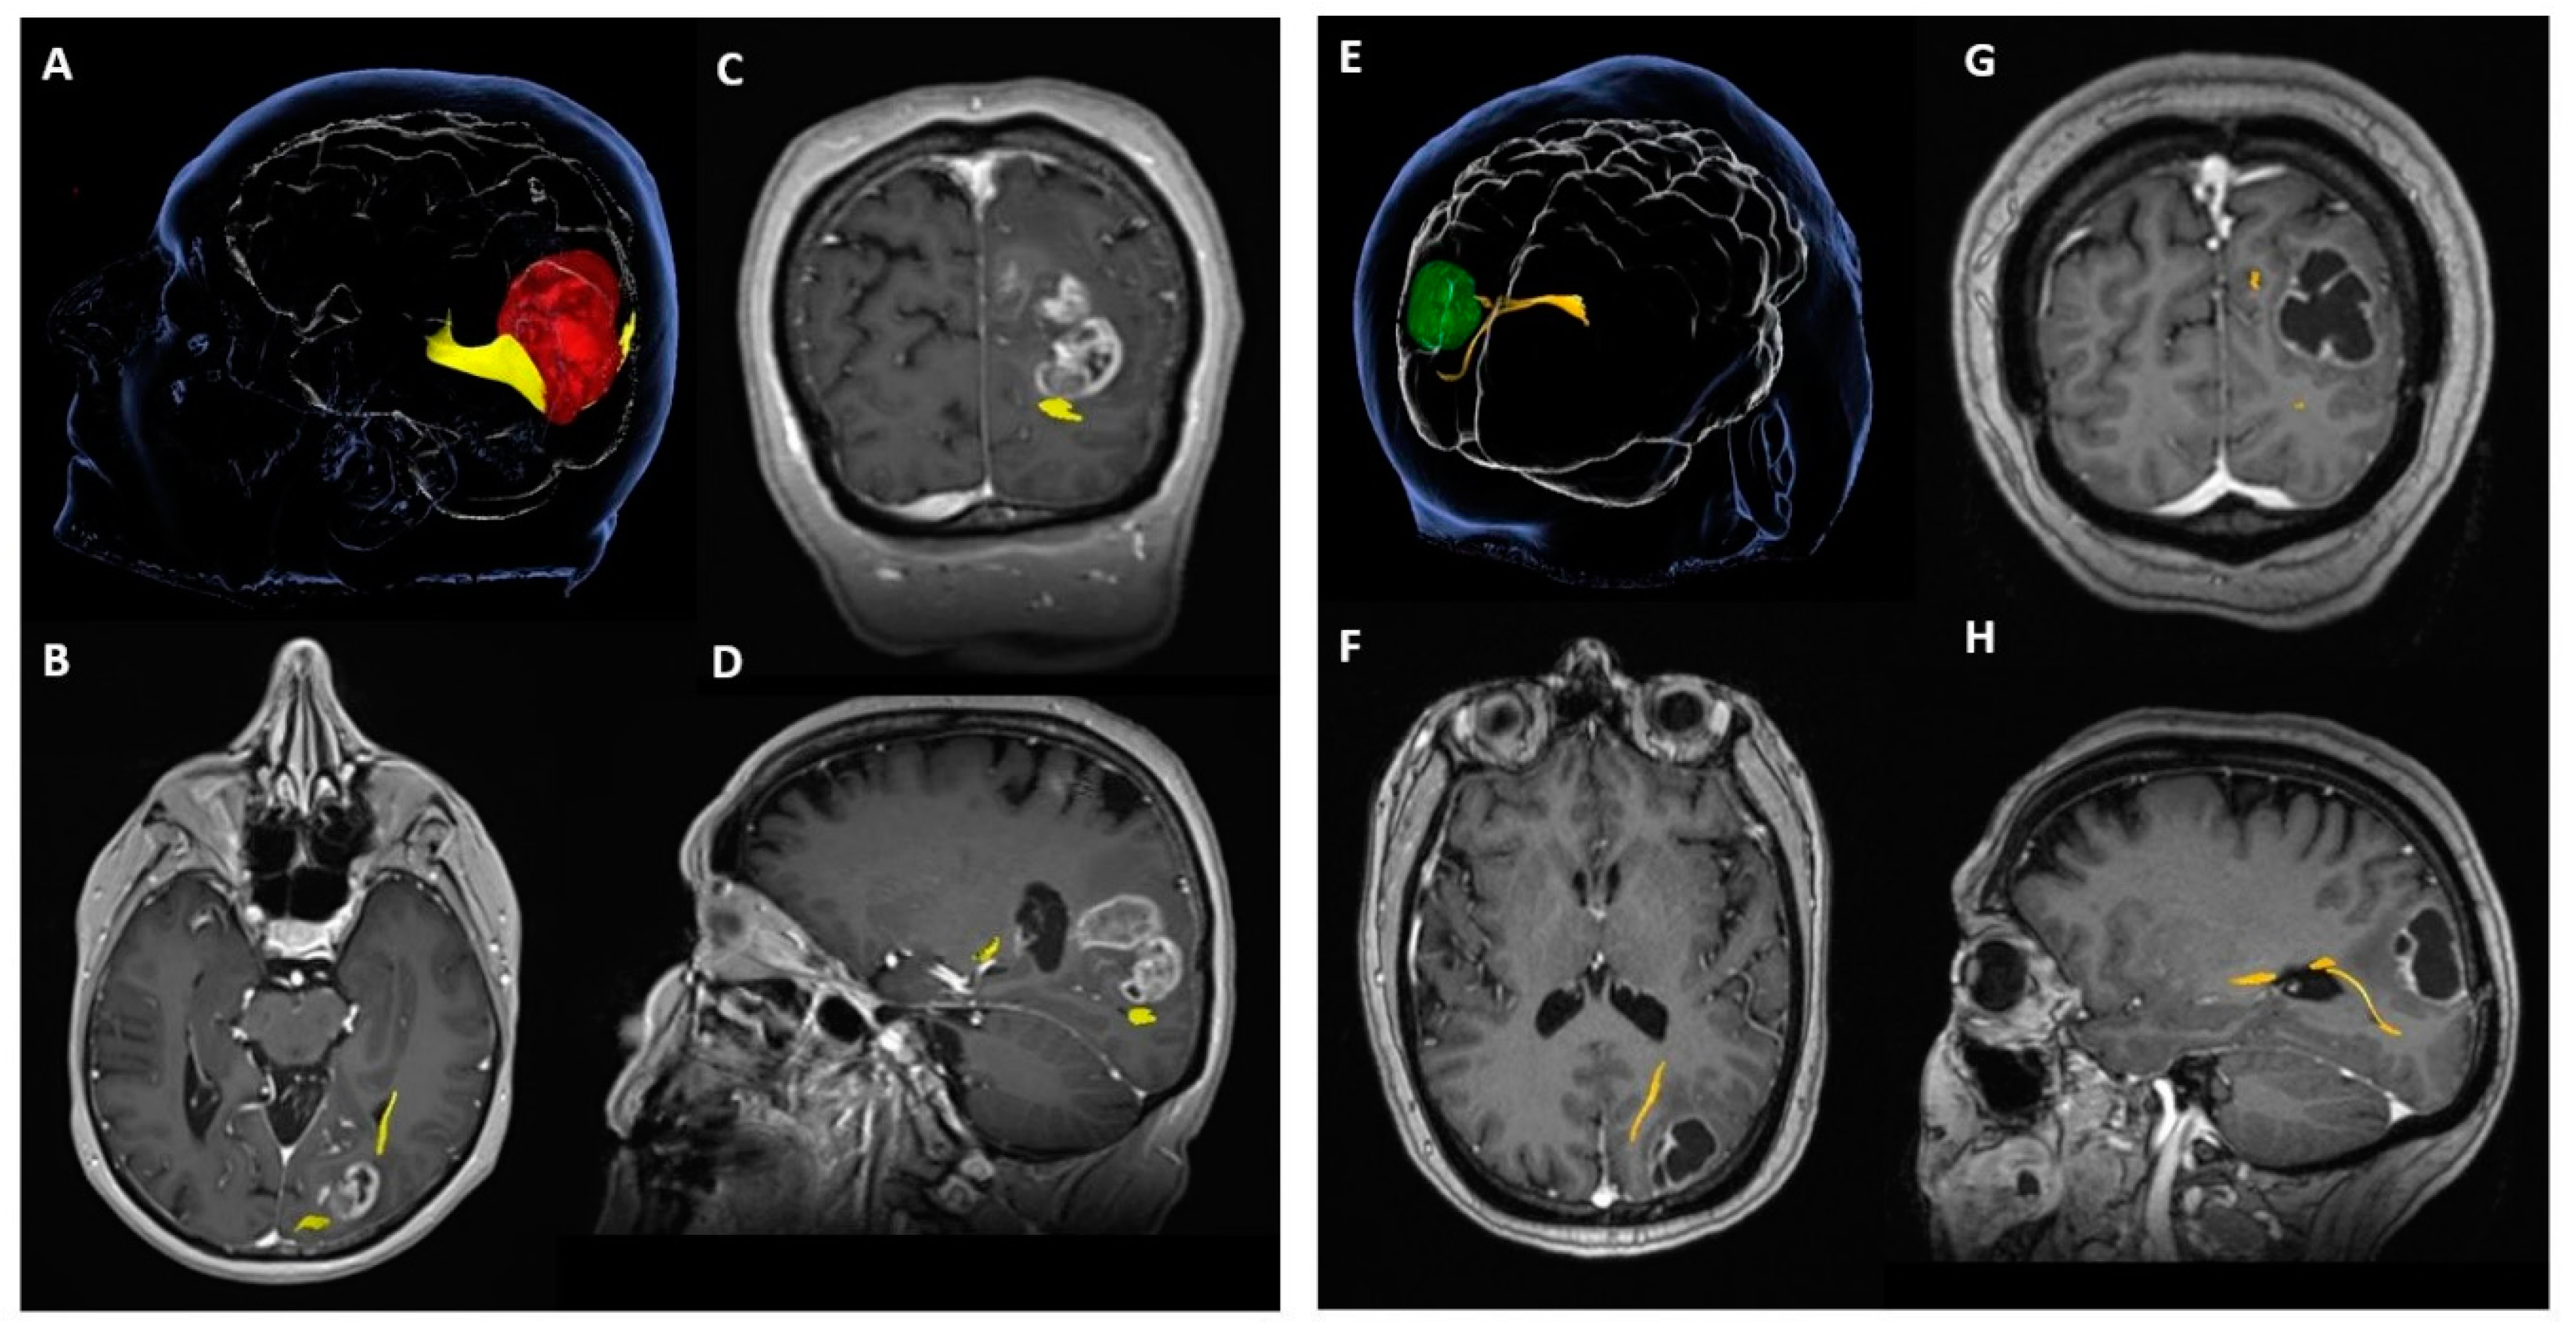

3.1. Preoperative Mapping

Tractography demonstrated that optic radiation was available for surgical planning in nineteen patients (48.72%) and tract invasion was identified in seven out of nineteen patients (36.8%). The availability of tractography for surgical planning was not related to a better VF outcome after surgery (p = 0.287) or a decreased likelihood of VF deterioration after surgery (p = 0.449). However, the preoperative documentation of optic radiation infiltration by the tumour (tumour-to-tract distance = 0 mm) was significantly related to VF deficit after surgery (p = 0.016) and a higher likelihood of postoperative VF deterioration (p = 0.040). (Table 2, Figure 3).

Figure 3. Example of two different tumours in the visual eloquent areas of the brain. (A) Probabilistic tractography of the optic radiation, infiltrated by the tumour (tumour—red, optic radiation—yellow); (B) axial T1-weightened MRI image post-gadolinium; (C) coronal view; (D) sagittal view; (E) probabilistic tractography of the optic radiation, displaced by the tumour without infiltration (tumour—green, optic radiation—yellow); (F) axial T1-weighted MRI image post-gadolinium; (G) coronal view; (H) sagittal view.